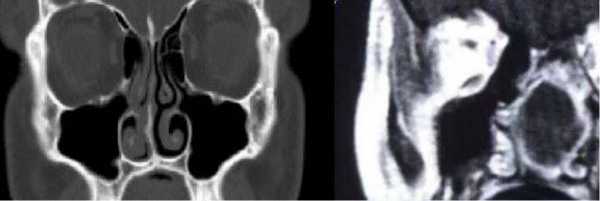

КТ (справа) и МРТ (слева) носовых пазух в коронарной проекции - фото

МРТ не подразумевает использование радиации для диагностики, поэтому более широко применяется у беременных женщин и детей. К каждому исследованию есть перечень показаний и противопоказаний, но оба метода визуализации в большинстве наблюдений являются взаимодополняющими. КТ показана для пациентов с кардиостимуляторами, имплантами, так как магнитное поле может привести к поломке приборов.

Для оценки опухолей придаточных пазух чаще проводят и КТ, и МРТ. Компьютерная томография обеспечивает качественную визуализацию деталей костной ткани, анатомические ориентиры у основания черепа. Магнитно-резонансное сканирование, по сравнению с КТ, лучше дифференцирует опухоль мягких тканей от воспалительного или геморрагического процесса, внутричерепные осложнения и метастатическую инвазию. При лимфоаденопатии шеи более показательна КТ. Чтобы избежать ненужных затратных исследований, лучше, если конкретный тип диагностики указывает лечащий врач. Если Вы решили пройти исследование самостоятельно, специалисты центра “Магнит” подскажут подходящий с учетом конкретной ситуации способ визуализации.